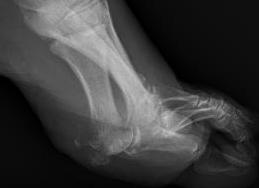

Forefoot - diabetic foot ulcer with evidence of underlying osteomyelitis

Hindfoot - calcaneal osteotomyelitis